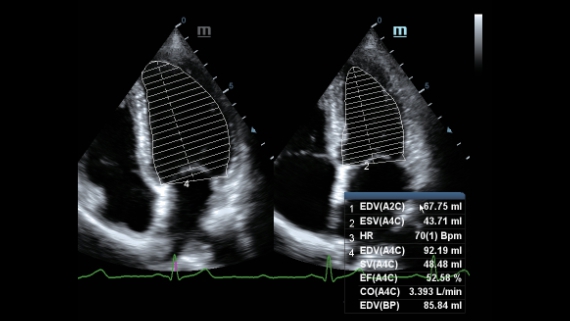

X-Insight ??? ??? ??? ??? ?? ??? ?? ?? ??????.

?????? ??? ???? ?? ???? ??? ??? ??? ???? ??? ??? ??? ?? ??? ???? ?????. ??? ?? ????? ???? ???? ??? ?? ??? ???? ?? ???? ??? ???? ???? ????.

???? ?? ??? ?????, X-Insight???? ??? DC-60 Exp ?? ??? ???? ???? ?? ??? ?? ??? ?? ???? ?????.

X-Insight??? ??? DC-60 Exp? ??? ??? ?? ?? ???? ???? ???(eXpress) ???, ???(eExceptional) ?????, ???? (eXceeding) ?? ??? ?? ????, ??? ???? ??? ??? ?? ???? ?????.